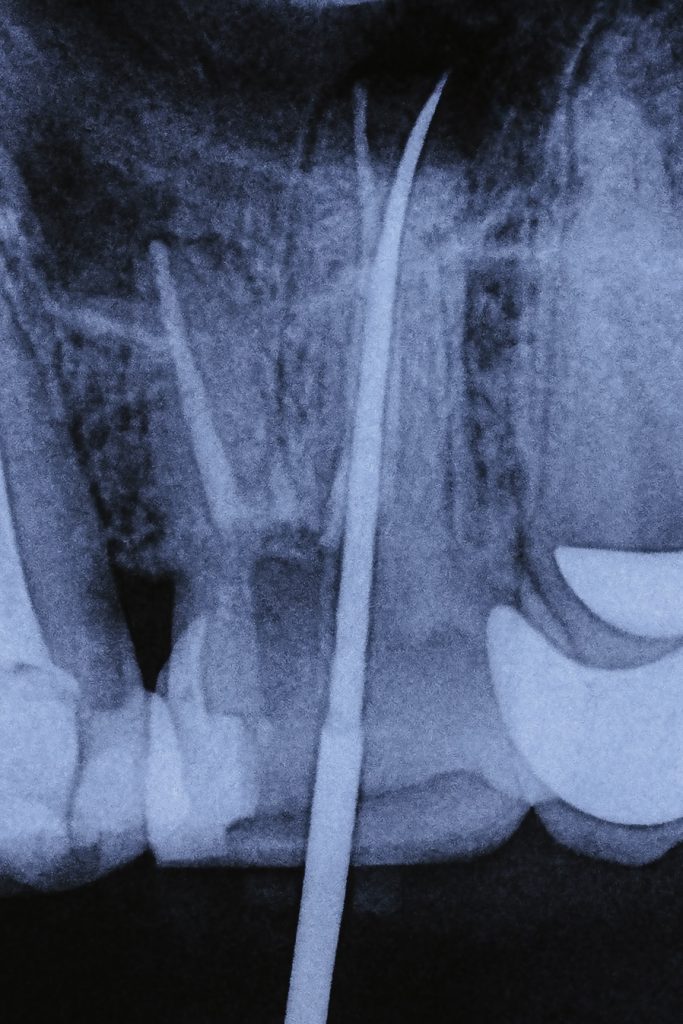

- Using pre-operative CBCT, the palatal root of the first molar was mapped for the suspected split.

- Under magnification, the canal division was identified and negotiated using C+ files and K-files #6–10 with EDTA gel.

- Working length was confirmed with an apex locator and radiographs.

- Rotary NiTi system was used for shaping; irrigants included 5.25 % NaOCl and 17 % EDTA, both sonically activated for effective disinfection. (Fig 3–4)